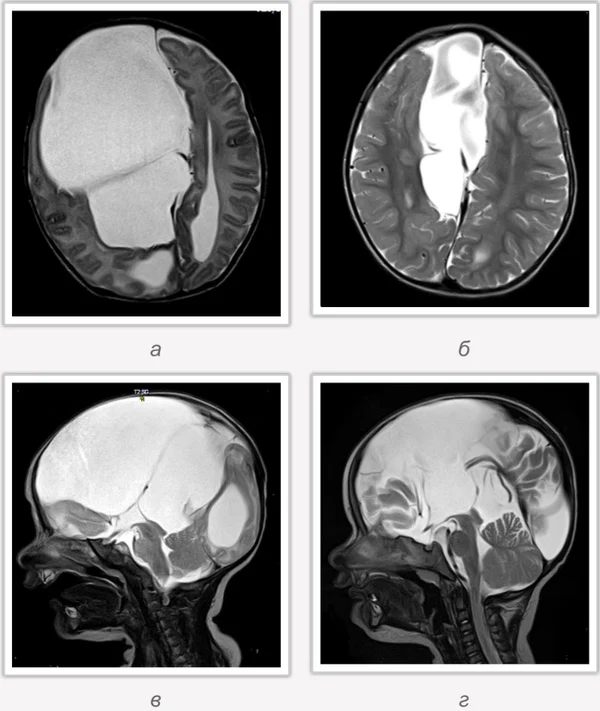

кисты, аномалии Денди-Уокера и др.Операции при внутричерепных кистах. В основном встречаются арахноидальные кисты различных локализаций и кисты сосудистых сплетений боковых желудочков. Пациентам с врождёнными кистами операции проводятся в следующих ситуациях: увеличении объема кисты в динамике, наличии клинических проявлений, компрессии и дислокации мозговых структур, наличии окклюзии ликворных путей. Нами используются 2 способа хирургического лечения кист: эндоскопическая перфорация стенок кист и открытая резекция кист. Открытая резекция кист проводится при ретроцеребеллярных арахноидальных кистах (рис. 2), при арахноидальных кистах межполушарной щели при отсутствии непосредственного контакта их стенок со стенками расширенных желудочков головного мозга и повторного увеличения кист средней черепной ямки после эндоскопической кисто-цистерностомии. Техника операции заключается в проведение краниотомии и максимальном иссечении стенок кист с созданием широкого сообщения кист с субарахноидальным пространством. Эндоскопические операции проводятся при арахноидальных кистах межножковой и пинеальной цистерн, арахноидальных кистах межполушарной щели при тесном контакте их стенок со стенками расширенной желудочковой системы (рис. 3), первично при арахноидальных кистах средней черепной ямки, а также при кистах сосудистых сплетений боковых желудочков. При арахноидальных кистах межножковой цистерны эндоскопически проводится перфорация стенок кисты, сообщая ее с просветом III желудочка и межножковой цистерной – эндоскопическая вентрикуло-кисто-цистерностомия (рис. 4). При арахноидальных кистах пинеальной цистерны проводится перфорация кисты в передне-верхних её отделах с созданием сообщения полости кисты с просветом III желудочка – эндоскопическая кисто-вентрикулостомия. С целью предотвращения облитерации сформированного отверстия иногда в полость кисты под контролем эндоскопа вводится стент перфорированный на протяжении (рис. 5, 6). Эндоскопическая кисто-цистерностомия выполняется при арахноидальных кистах средней черепной ямки. При этом создается широкое сообщение кисты с базальными цистернами. При кистах сосудистых сплетений боковых желудочков проводится их вскрытие в просвет боковых желудочков – эндоскопическая кисто-вентрикулостомия. При множественных кистах проводится их хирургическое сообщение между собой – интеркистосмия